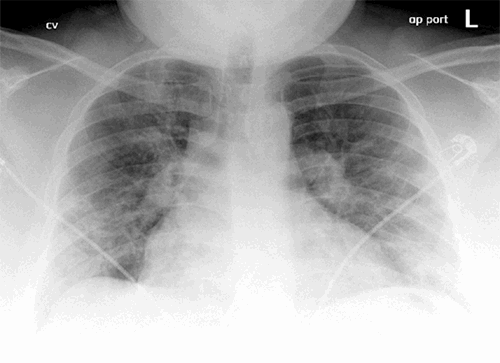

We report a case of a 30-year-old woman (gravida 2, para 1) at 35 weeks' gestation who developed respiratory symptoms and was tested positive for SARS-COV-2 (severe acute respiratory syndrome coronavirus 2) virus by nasopharyngeal polymerase chain reaction (PCR) assay. Her medical history includes morbid obesity with a BMI of 38 and hypothyroidism. The patient developed worsening shortness of breath and presented to the emergency room at an outside institution about one week after testing positive. Her imaging was consistent with acute respiratory distress syndrome (ARDS) from COVID-19 pneumonia (Figure 1).

Figure 1. Chest X ray of the patient on initial presentation showing development of COVID-19 associated acute respiratory distress syndrome